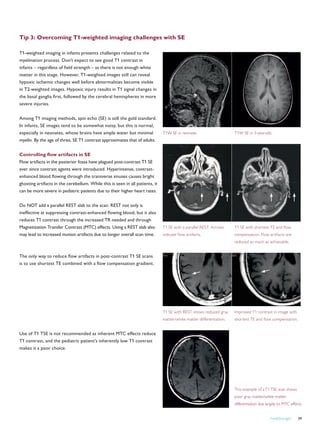

Versailles clinic lightens up

its MRI room

Ambient Lighting creates a calming and relaxing atmosphere in Panorama HFO examination room

Philips Healthcare has installed the first Ambient Lighting MR suite in the Clinique Medicale

de la Porte Verte, Versailles, France. This private clinic, which is located west of Paris,

focuses on elderly patients and delivers acute care, re-education, and aftercare services.

To maintain its prestigious reputation, the

clinic decided to buy a Panorama HFO

MRI system. In addition, the clinic installed

the Ambient Lighting solution to further

enhance the patient-friendly experience

offered by the wide open Panorama HFO.

In close cooperation with the clinic, Philips

had directed preparatory discussions and

provided architectural recommendations

for the room. A local contractor smoothly

installed the Ambient Lighting MR solution

in just two days.

The clinic’s staff reports that patients are